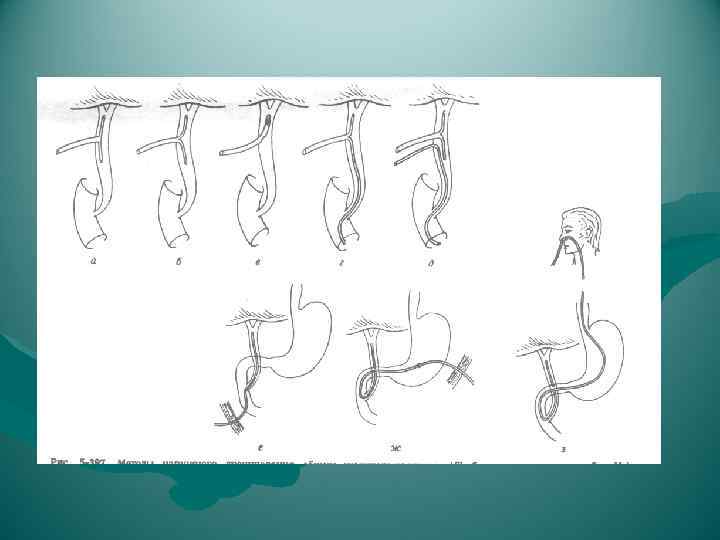

Родственная трансплантация правой доли печени Билиарная реконструкция Гепатико-гепатикостомия ductus hepaticus Бихолангио-гепатикостомия + гепатико-цистикостомия

Родственная трансплантация правой доли печени Билиарная реконструкция Гепатико-гепатикостомия ductus hepaticus Бихолангио-гепатикостомия + гепатико-цистикостомия

Варианты слияния протоков

Варианты слияния протоков